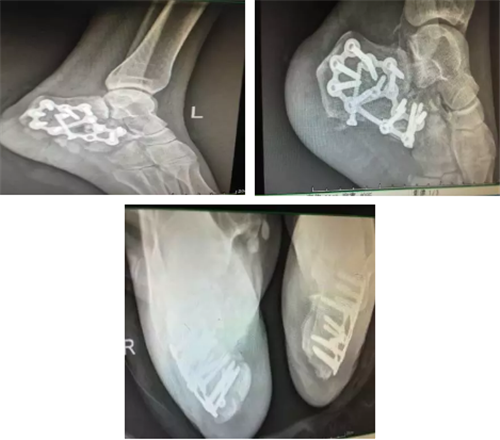

| 2017年11月20日,郴州市第四人民医院骨科主任谭宜昌带领其团队应用3D打印技术成功为一双侧跟骨粉碎性骨折患者实施了手术,术后患者恢复良好。 该患者为一年轻女性,自高处坠落导致双侧跟骨粉碎性骨折,骨折移位较大,为复杂型骨折。对于该疾病使用过去传统影像学方法难以直观了解骨折情况,尤其是年轻医生较难准确对骨折进行评估和分型。模拟手术多在二维图纸或者术者的脑海中进行,在实际手术操作中也只能凭经验进行操作,凭经验选择置入物的规格,并现场将置入物进行折弯、剪裁,调整成较为合适的尺寸。且螺钉方向也只能依靠医生的解剖知识及经验进行确定。这种经验性手术操作准确性较差,过程复杂,耗时长,透视多,创伤大。 而通过3D打印技术将患者术前跟骨CT平扫加三维重建产生的DICOM数据经计算机处理,修改后获得打印模型的标准格式数据,连接3D打印机,根据需要选择不同类型的3D打印技术进行三维物理模型打印。利用该项技术打印出来的骨折模型非常准确,为患者和医生提供了较为直观的触觉与视觉上的体验,能提高医生与患者及家属交流的效果,能为手术方案的设计和制定以及术前演练提供有力的参数和依据,需要多长的钢板,需要几颗螺钉,医生在术前就能心中有数。这不仅大大提高了手术的精确度,提高手术效果,而且还能有效减小创伤,减少术中出血,节省手术时间,缩短患者术后恢复时间,为患者节省医疗费用。

术后X线